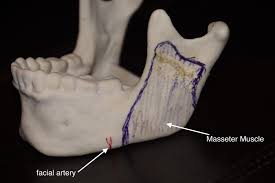

The masseter sits along the lateral surface of the ramus and angle. So if someone were to have bilateral condyle ramus replacement, and the ramus portion of the prosthesis were designed with more lateral fullness, then in theory the soft tissue over that area, including the masseteric region, could sit more laterally as well.

I am talking more specifically about the upper/lateral ramus region and whether widening that area could influence the appearance of the upper masseteric zone and overall lower third width.

Second, the masseter is not a solid block that just gets “pushed out.” It is a living muscle. It heals, adapts, scars, changes tension, and sits within a soft tissue envelope that is different in every patient. So the visual result would probably be less clean and less predictable than people imagine.

Third, once you start adding lateral bulk, you are not only changing appearance. You are potentially changing soft tissue drape, the way the muscle lies on the ramus, hardware relationships, fixation considerations, and load transfer through the construct. A design that seems appealing on a cosmetic level could create trade offs biomechanically.

The masseter sits along the lateral surface of the ramus and angle. So if someone were to have bilateral condyle ramus replacement, and the ramus portion of the prosthesis were designed with more lateral fullness, then in theory the soft tissue over that area, including the masseteric region, could sit more laterally as well.

I am talking more specifically about the upper/lateral ramus region and whether widening that area could influence the appearance of the upper masseteric zone and overall lower third width.

Second, the masseter is not a solid block that just gets “pushed out.” It is a living muscle. It heals, adapts, scars, changes tension, and sits within a soft tissue envelope that is different in every patient. So the visual result would probably be less clean and less predictable than people imagine.

Third, once you start adding lateral bulk, you are not only changing appearance. You are potentially changing soft tissue drape, the way the muscle lies on the ramus, hardware relationships, fixation considerations, and load transfer through the construct. A design that seems appealing on a cosmetic level could create trade offs biomechanically.